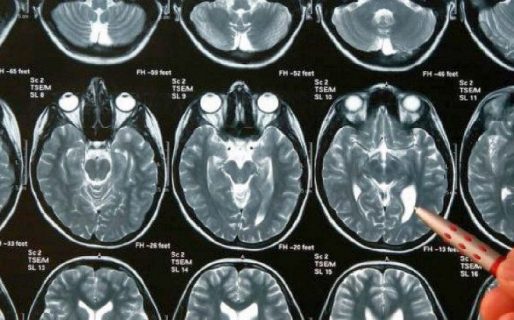

Un tumor cerebral es una masa o bulto de células anormales que se encuentra en el cerebro. Existen varios tipos de tumores cerebrales. Algunos tumores cerebrales no son cancerosos (benignos) y algunos tumores sí lo son (malignos), explica la prestigiosa Clínica Mayo. Este último, el maligno, fue el cáncer que le tocó padecer a Gerardo Rozín, reconocido periodista, productor y presentador de radio y televisión argentino que falleció en la noche del viernes.

Según aclara el sitio médico estadounidense, los tumores cerebrales se pueden originar en el cerebro (tumores cerebrales primarios) o el cáncer se puede originar en otras partes del cuerpo y luego extenderse hasta el cerebro (tumores cerebrales secundarios o metastásicos).